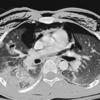

9a bilat see CT